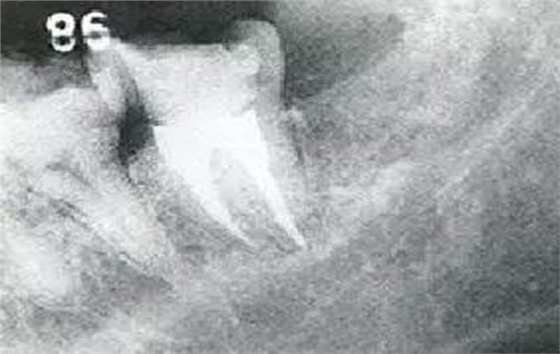

●參考病例② 25歲女性

25歲女性。菌斑控制狀態(tài)不好。齦溝除磨牙處外全在3mm以下,X光照片上左上、右下、左下的第一磨牙上有垂直性骨吸收。這個(gè)病例是參考病例①10年前的狀態(tài),是典型的侵襲性牙周炎局部型。

牙周病的發(fā)展因部位不同而發(fā)展程度不同的。10點(diǎn)后的狀態(tài)參考病例①和參考病例②的磨牙處的狀態(tài)相比較,思考下沒接受治療病情發(fā)展的特別性吧。

在左下第一磨牙在25歲時(shí)近中處可以看到垂直性的骨吸收,但35歲時(shí)吸收停止,原本沒有見到的遠(yuǎn)中處骨吸收的,現(xiàn)在卻吸收得很嚴(yán)重。

在右下處,原本有大量骨吸收的第一磨牙處的吸收卻變緩慢,原本沒有吸收的第二前磨牙卻出現(xiàn)了吸收。出現(xiàn)吸收的左上第一磨牙的遠(yuǎn)中處,吸收得越來越多了。